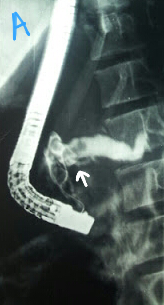

Pancreatic duct calculi

This 12 year old girl had a history of multiple episodes of pancreatitis secondary to pancreatic ductal calculi. On ERCP the pancreatic duct was cannulated followed by contrast injection which initially outlined negative shadows in the head region (A: white arrow). However further contrast injection showed the duct full of calculi (B: white arrows). We didn't attempt to remove. The patient was referred to the surgical team for further management.